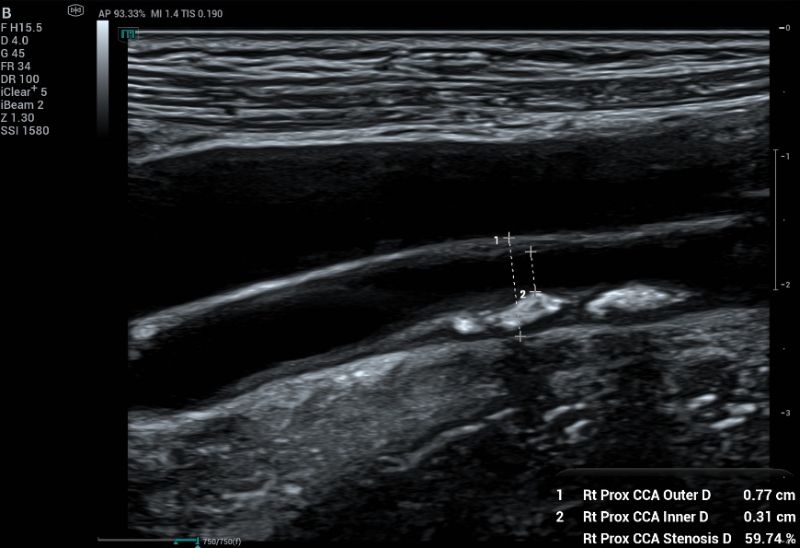

A 50-year-old female came for health screening with no symptoms. Carotid ultrasound assessment was done bilaterally. A plaque measuring 2.36 x 0.34 cm (Figure 1) was found on the right distal CCA.

To measure percentage of stenosis, diameter-based measurement (Fig 3) remains the most widely accepted method to quantify carotid stenosis. However, for plaques that are non-circular or crescent-shaped in cross-section, a single diameter measurement can significantly underestimate the true severity of the narrowing.

Measuring percentage of stenosis using diameter-based method.  This method measures the full vessel lumen and patented lumen.

Fig.3: Measuring percentage of stenosis using diameter-based method. This method measures the full vessel lumen and patented lumen.